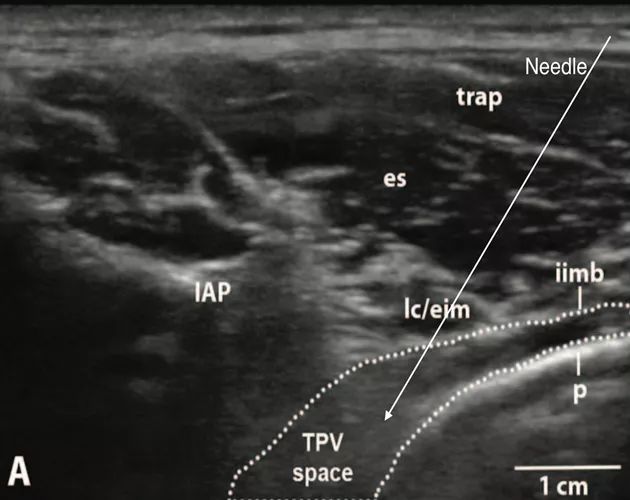

b.重点介绍“IAP外向平面内入路”。其超声影像及相关解剖如下[2]:

(TPV space:胸椎旁间隙,IAP:下关节突,iimb:肋间内膜,SCTL:上位肋横突韧带,p:壁层胸膜,es:竖脊肌,trap:斜方肌,lc/eim:肋提肌/肋间外肌,ST:交感干。Anesthesiology 2015; 123:459-74)